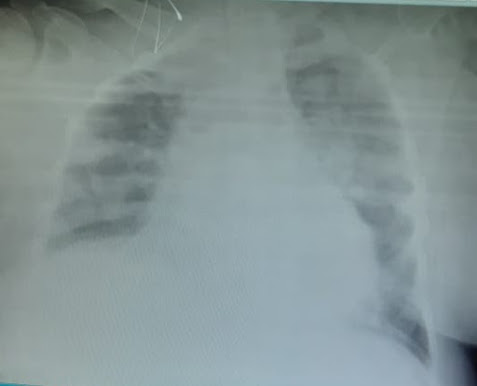

Chest x ray:

Expiratory field, PA view showing cardiomegaly and prominent bronchiovascular , hazziness, effusion